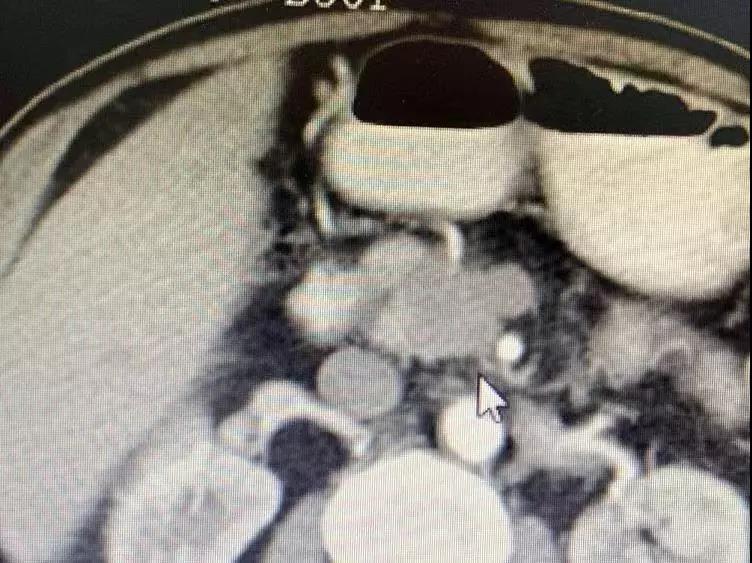

До операции опухоль поджелудочной железы окружает кровеносные сосуды и обнаруживаются метастазы в брюшных лимфатических узлах.

Медсестра сказала мне, что он и его семья были очень добрыми, и они улыбались и кивали вам, когда приветствовали. Было сказано, что он внезапно почувствовал боль в верхней части живота в апреле этого года. Позже в мае он прошел обследование в местной больнице. Неподтвержденная масса в поджелудочной железе размером 3 см была обнаружена вблизи верхней брыжеечной вены, которая предположительно была раком поджелудочной железы. 25 июля у него было еще одно обследование, и его состояние ухудшилось. Опухоль проникла в верхнюю брыжеечную вену и артерию; многочисленные маленькие лимфатические узлы были обнаружены перед полой веной и вблизи аорты. Из-за ограниченных медицинских ресурсов лучшего лечения в Непале не было. Затем его врач порекомендовал ему Онкологическую больницу Фуда.

Необратимая электропорация при опухоли поджелудочной железы

Для дальнейшего лечения как можно скорее его сын привез его в Онкологическую больницу Фуда 31 августа. После обследования ему был поставлен диагноз несоциализированная аденокарцинома III стадии в поджелудочной железе и диабет II типа с множественными узлами в печени, легких и щитовидной железе. После обсуждения с доктором Ню Личжи и медицинской командой он и его семья согласились провести катетеризацию в подключичной вене 6 сентября и на сдедующий день необратимую электропорацию при опухоли поджелудочной железы. После интенсивной терапии его состояние улучшалось с каждым днем.